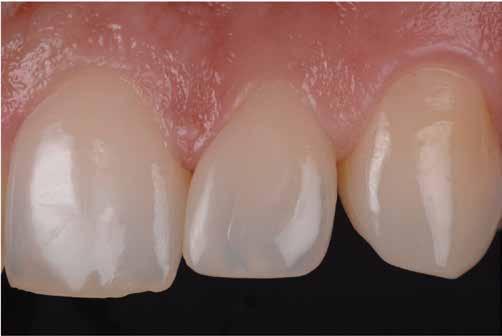

ezen a területen, a fogászat profitál az ilyen fejlesztésekből, és ma már számos kezelési megoldást kínálunk pácienseinknek. Rezidens korom alatt klinikai szakfelügyelőként dolgoztam akadémiai környezetben, ahol elsősorban kivehető fogpótlásra szoruló geriátriai betegeket kezeltem, valamint olyanokat, akiknek fix fogpótlásra, például fog- vagy implantátummal ellátott hagyományos rögzített fogpótlásra (azaz korona és híd) volt szükségük, elsősorban arany vagy fémkerámia felhasználásával. Az ezekben az években megfigyelt klinikai kudarcok és a beavatkozások invazív jellege, nevezetesen a foghúzásra vonatkozó több fúrás és egyszerűbb döntések jelentős szerepet játszottak a kutatási irányvonalam kialakításában az évek során. Ez volt az az időszak is, amikor elkezdtem többet foglalkozni az adhezív fogászattal, ami megváltoztatta a protetikai fogászat klasszikus arculatát, és határozottan kevésbé invazívvá tette azt (1. a-d ábrák). Ma, az intenzív transzlációs és klinikai kutatás eredményeként, különös tekintettel a fogászati bioanyagok alkalmazására, klinikai szakértelmem a minimálisan invazív, adhezív eljárások alkalmazására összpontosít a protetikai fogászatban, a szövődmények kezelésére és a költséghatékony kezelési lehetőségek felkínálására.

1. a-d ábrák: a) Fogerózió a molárisok okkluzális felszínén, b) maratás foszforsavval, c) minimálisan invazív műgyanta-kompozit fedőréteg levegővel történő felszívása, d) adhezív ragasztott fedőréteg a hiányzó zománc és dentin helyreállítására.